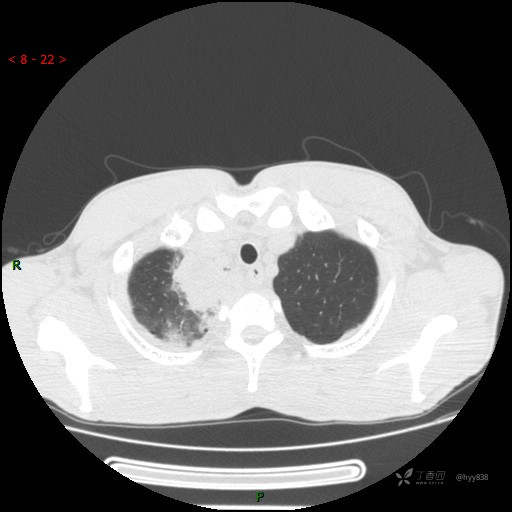

胸部CT平扫